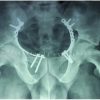

On follow-ups at interval of 6 weeks, at the end of 6 months (Fig. 3, 4), the fracture showed signs of non-union. A decision of supplementary fixation and bone grafting was made. Keeping the lateral plate in-situ, an additional pre-bent 4.5 narrow Dynamic Compression Plate (DCP) was applied on the medial side and bone grafting from the right iliac crest was done at the fracture non-union site (Fig. 5).

Follow-up X-rays at 6 weeks (Fig. 6) and 5 months (Fig. 7) post-second surgery showed good amount of callus and consolidation, proving that the intervention was a right decision. After 2½ years, the present X-rays (Fig. 8) show fracture completely consolidated and no implant-related problems. Patient is able to walk without support and without the caliper. He uses the same shoe raise and has good knee range of movements of 0–100o (Fig. 9). There are no pain or any other local complaints.